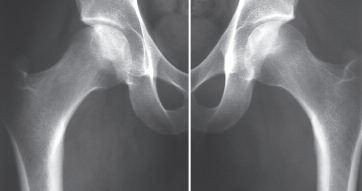

1. 主要体征X 线表现股骨头塌陷,股骨头内有硬化带(分界线),软骨下有新月征,无关节间隙狭窄,髋臼无异常见(图1)。

图1 X 线表现股骨头内有硬化带,软骨下有新月征